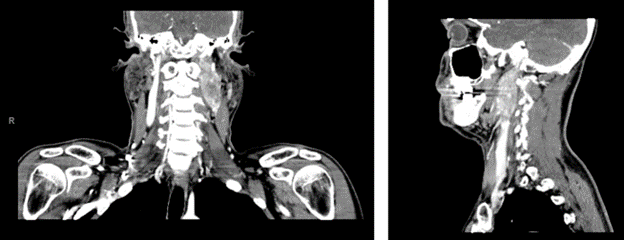

Given the patient’s symptoms, his PCP ordered a neck ultrasound, which showed a left cervical level II heterogenous hypoechoic vascular mass located within and expanding the carotid sheath with the superficial visible surface measuring 2.9 x 1.2 x 2.0 cm. This prompted a CT of the head and neck with IV contrast, which showed a large mass extending from the level of the left carotid bifurcation superiorly to the left skull base with encasement of the left internal carotid artery with the mass measuring 4.3 x 2.0 x 2.1 cm, with suspicion for paraganglioma; CT also showed several enlarged lymph nodes on the left with the largest being 1.1 cm in the level IIB region (see image 1). At this time, the patient was referred to endocrinology at a satellite UPMC facility as well as ENT.

Image 1. CT scan with contrast of head and neck showing the left carotid sheath paraganglioma.